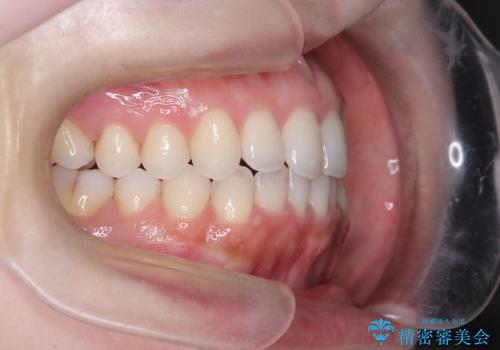

【インビザライン】オープンバイトを治したい

- 前歯の凸凹を主訴に来院された患者様です

骨格性の下顎前突傾向もあったため、臼歯関係の遠心移動も行うことで綺麗な仕上がりで矯正を終了することができました。

遠心移動を行うことで期間はかかりましたが、良い状態で仕上がっています。